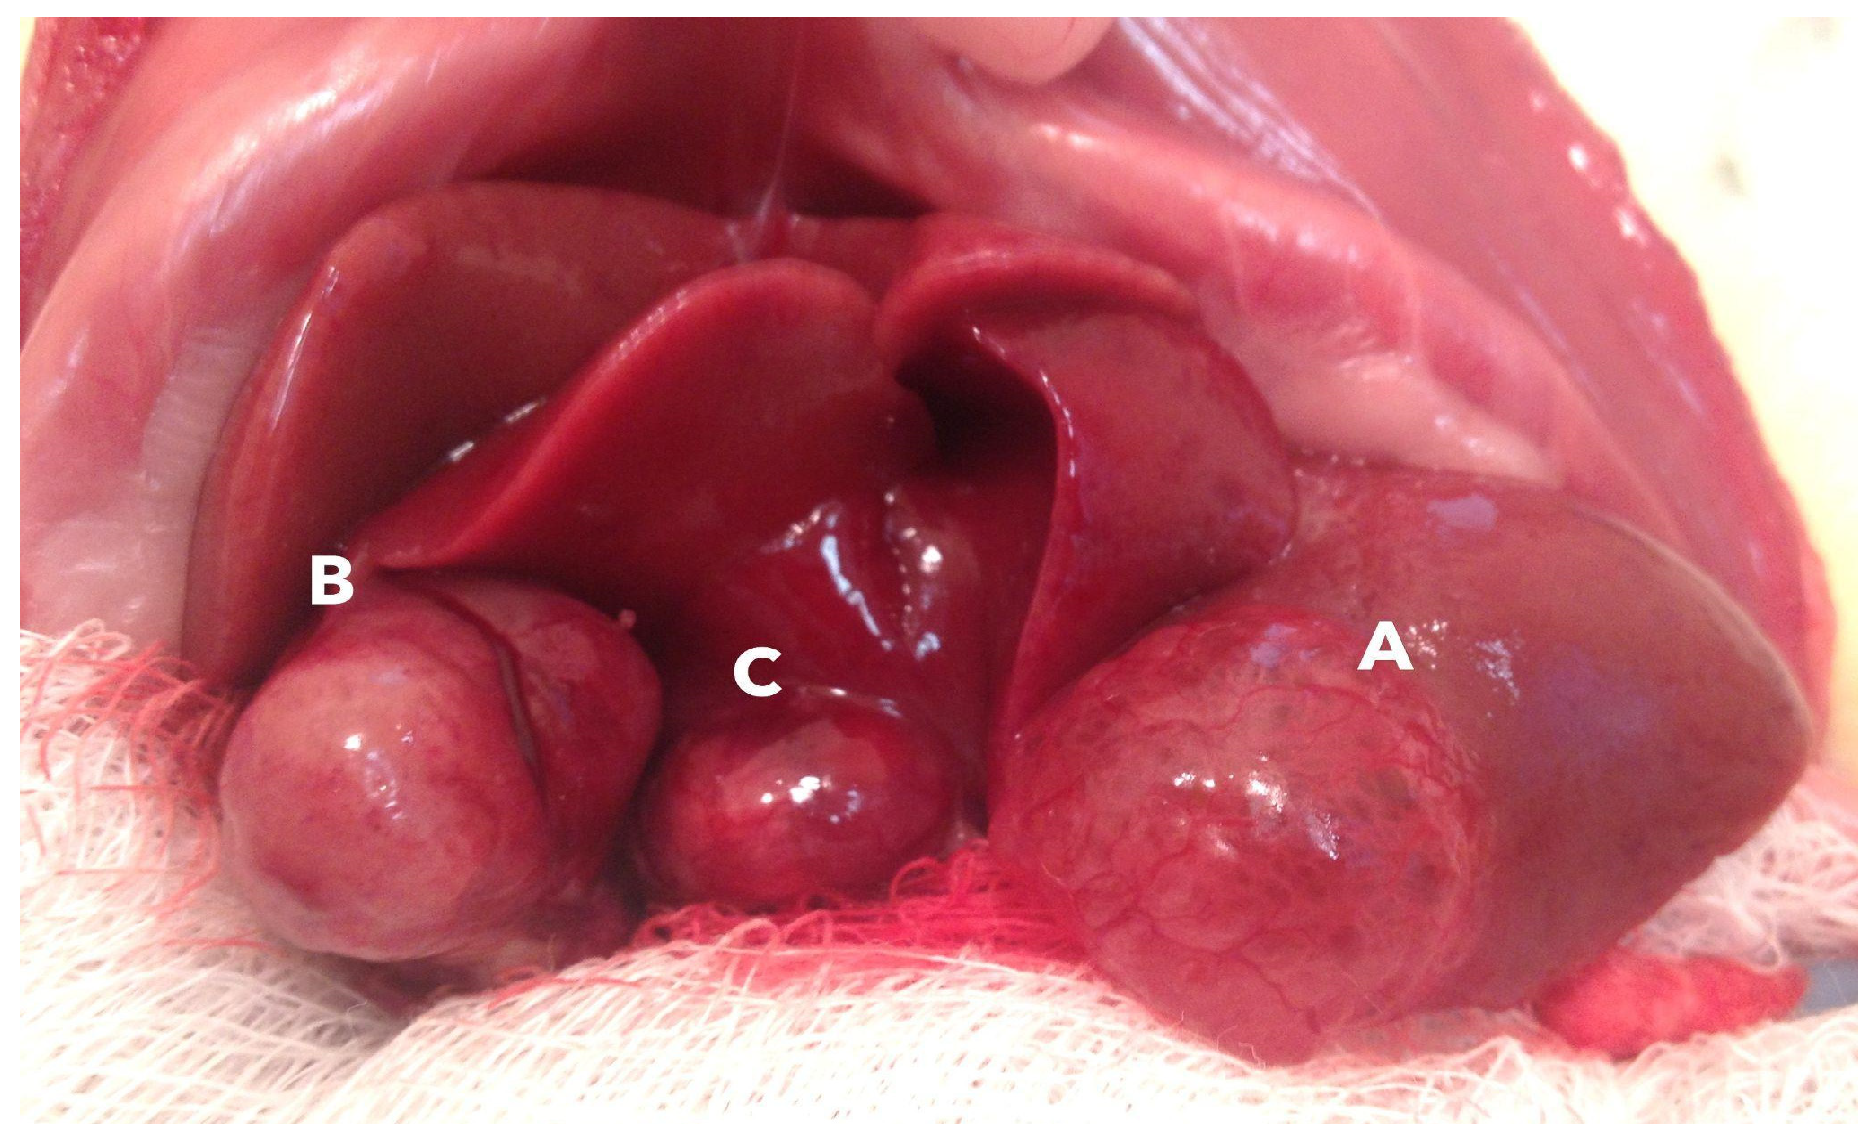

2.1. General Lesion Features

2.2. Morphology